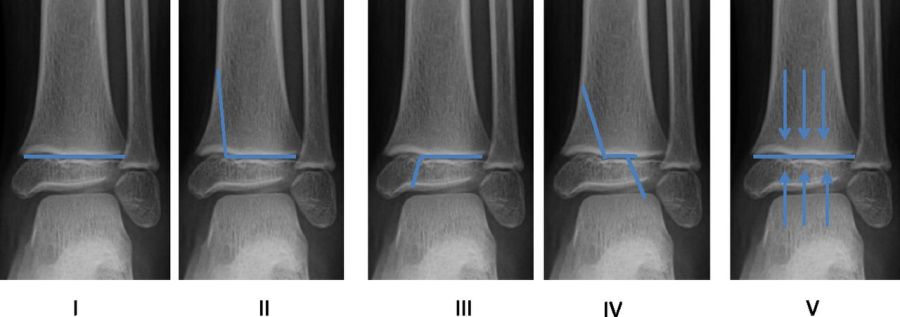

Salter-Harris classification of physeal fractures: I through physis; II through physis and metaphysis (most common); III through physis and epiphysis; IV through all three; V crush injury of physis

Salter-Harris classification — Types I–V

Type Description Growth Arrest Risk

I Through physis only — periosteal sleeve; X-ray may be normal Low — physis intact

II Through physis + metaphysis (most common; Thurston-Holland corner fragment) Low — most common type; favorable prognosis

III Through physis + epiphysis (intra-articular; surgical) Moderate — articular involvement

IV Metaphysis + physis + epiphysis (crosses entire plate — surgical) High — crosses entire growth plate

V Crush/compression of physis (poor prognosis; often missed acutely) Highest — physeal destruction